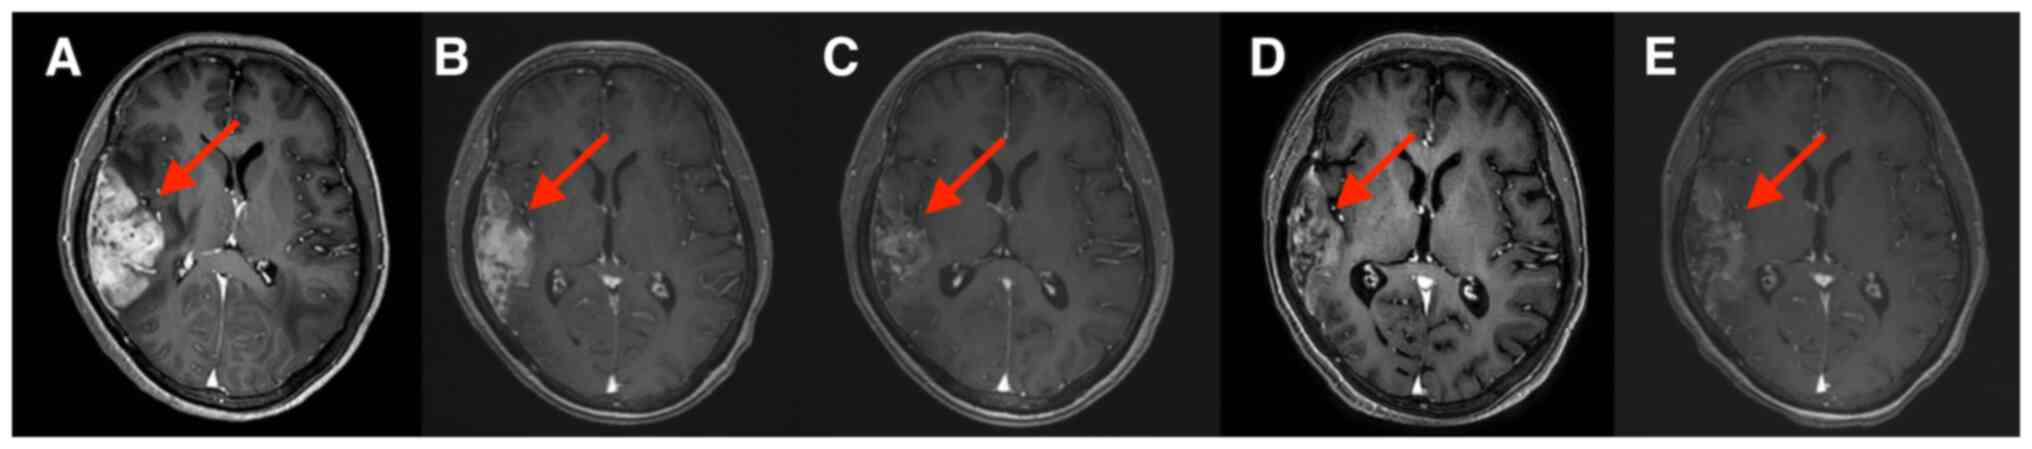

Although human epidermal growth factor receptor 2 (HER2)‑targeted therapy significantly improves the prognosis of patients with HER2‑positive breast cancer, most patients with advanced breast cancer eventually progress due to drug resistance. At present, there is no standard treatment after patients become resistant to HER2‑targeted therapy. Previous studies have indicated that anti‑angiogenesis drugs have potential efficacy in the treatment of advanced breast cancer. The present study reported on a case of a pretreated patient with HER2‑positive advanced breast cancer with brain metastases who developed resistance to multiple lines of HER2‑targeted treatment. The patient was treated with apatinib combined with trastuzumab and albumin‑bound paclitaxel. The patient achieved partial response to the third‑line treatment with a progression‑free survival of 9 months. After combination treatment, the symptoms of headache and vomiting were relieved and all the brain metastases were significantly reduced. The present case indicated that apatinib may have anti‑tumor activity in patients with HER2‑positive breast cancer with HER2‑targeted drug resistance. The present case provides valuable information and may offer a new possibility for the treatment of patients with breast cancer with brain metastases who progressed after clinical treatment with small‑molecule anti‑HER2 tyrosine kinase inhibitor drugs.

Figure 3